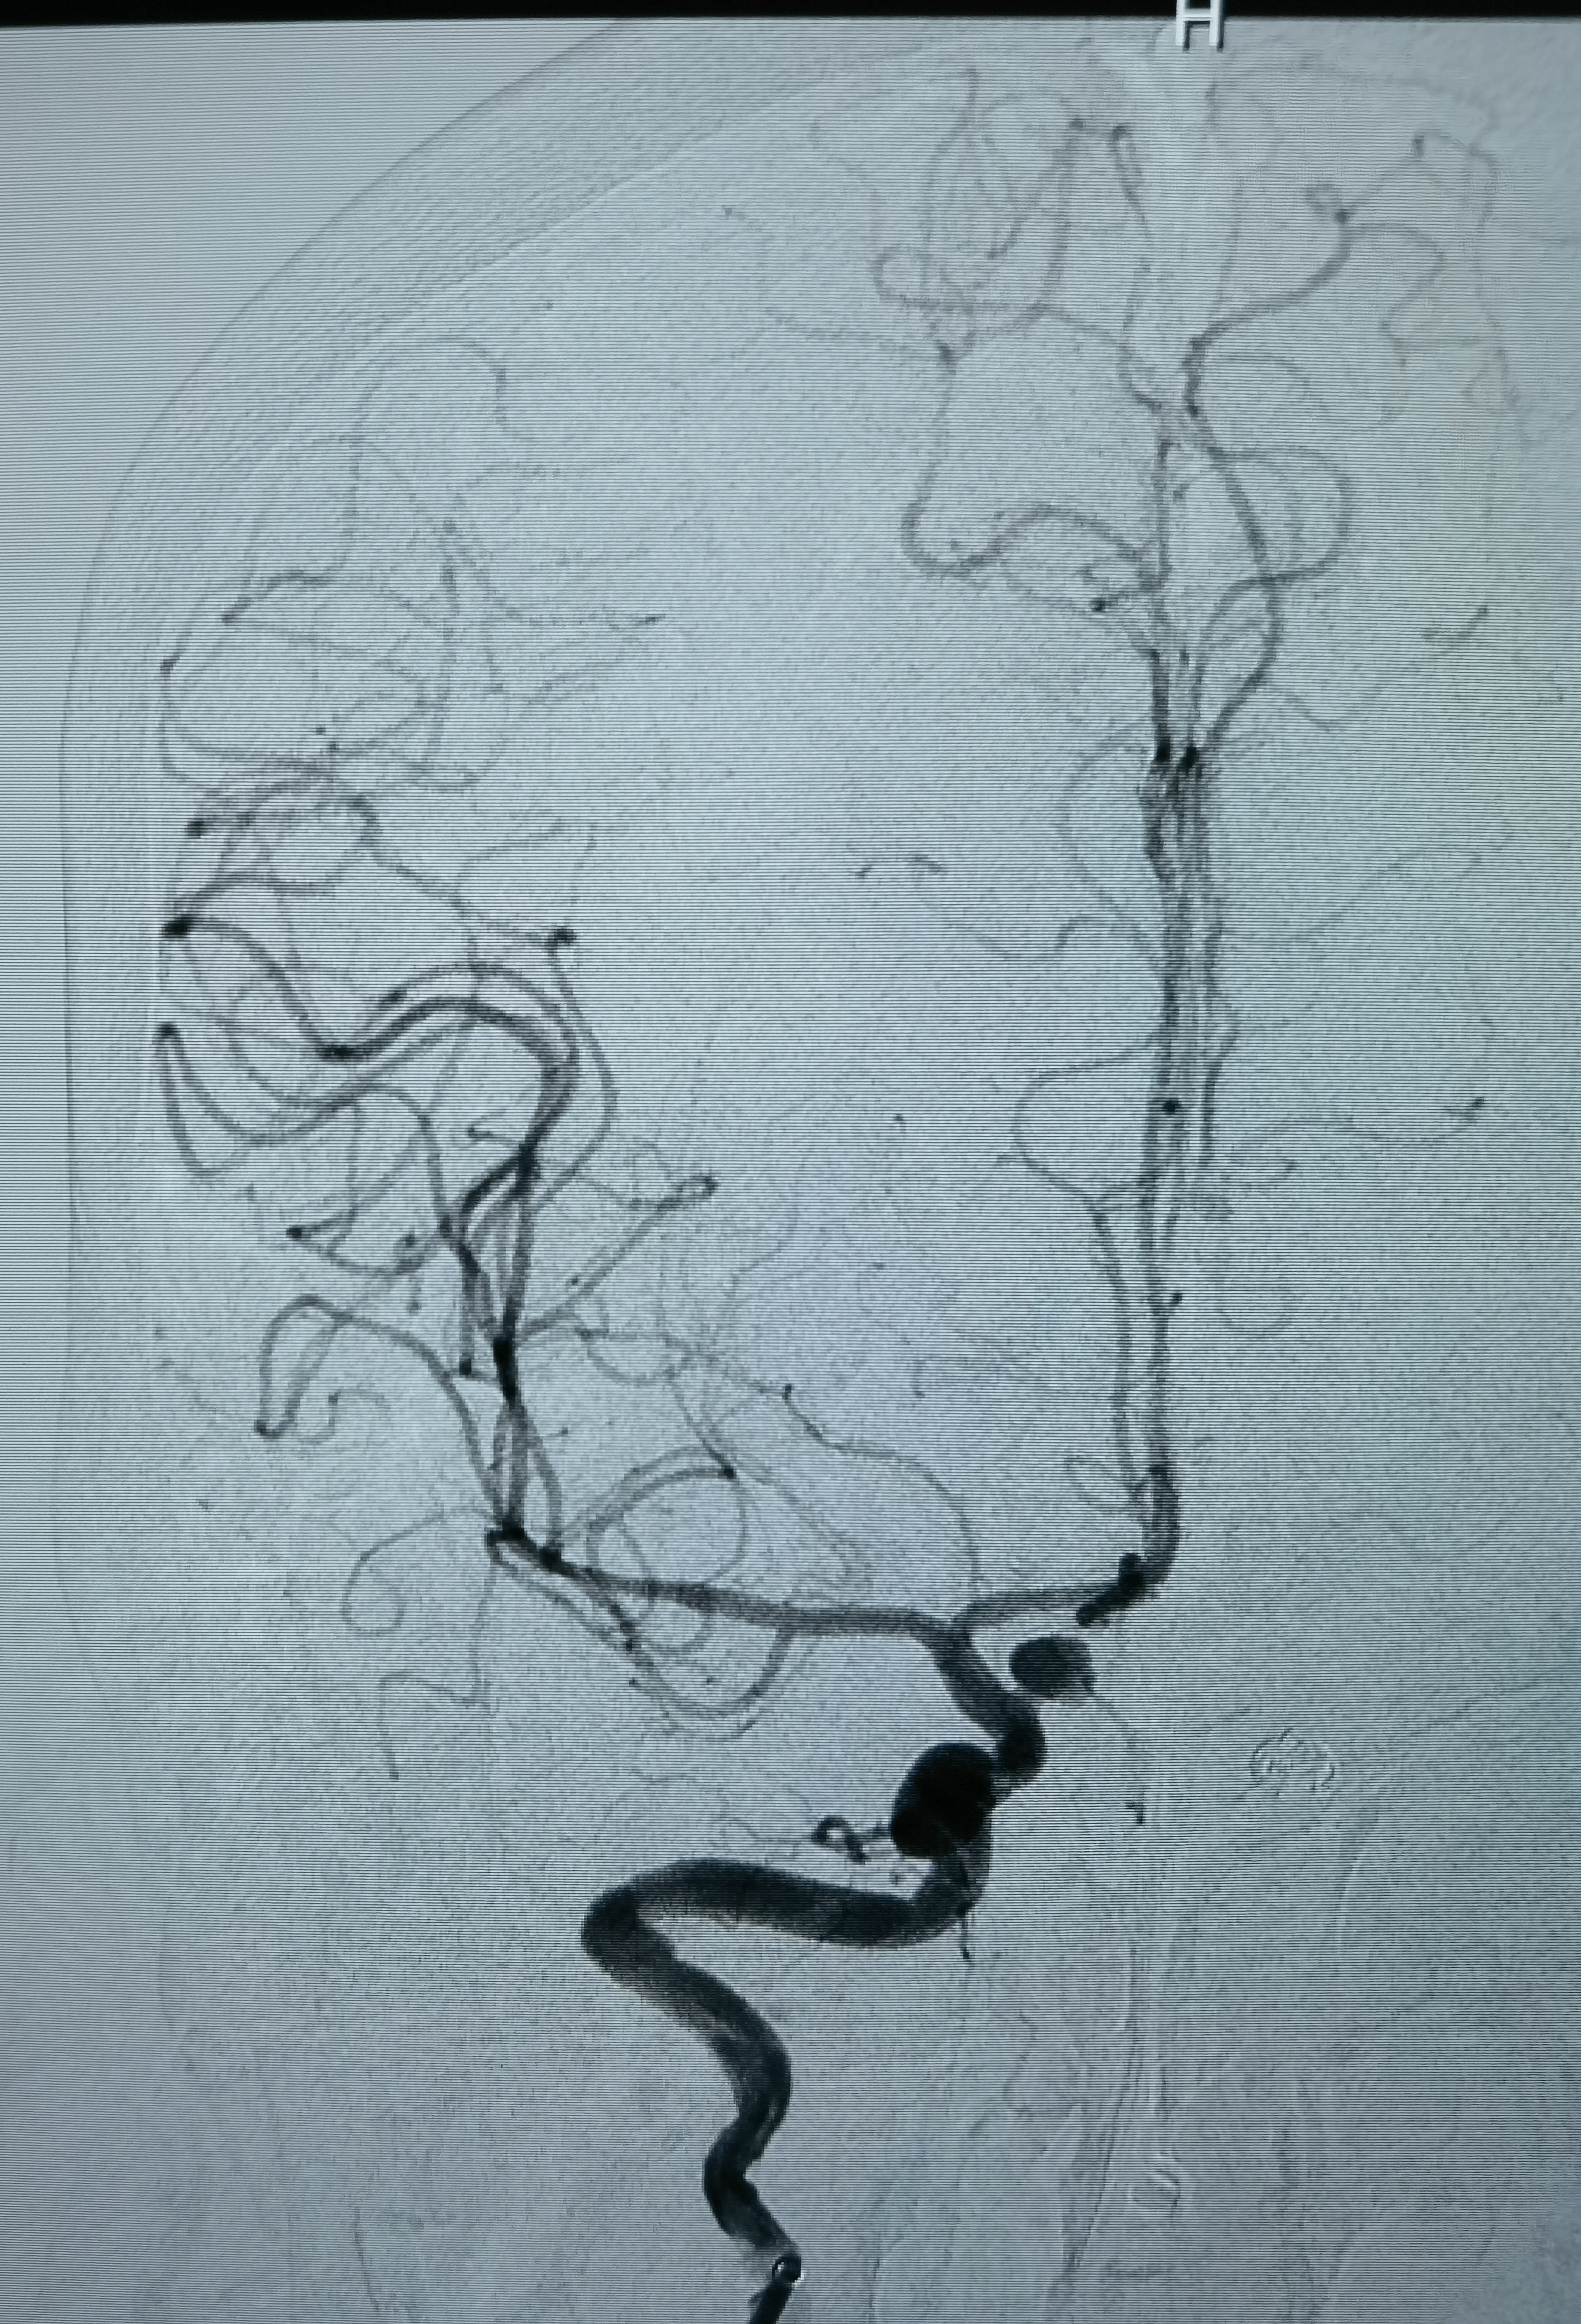

三维旋转造影

第三次出血后急诊上台,造影显示动脉瘤增大

工作位造影,瘤体约6.1*5.5mm,更加确认是血泡样动脉瘤!